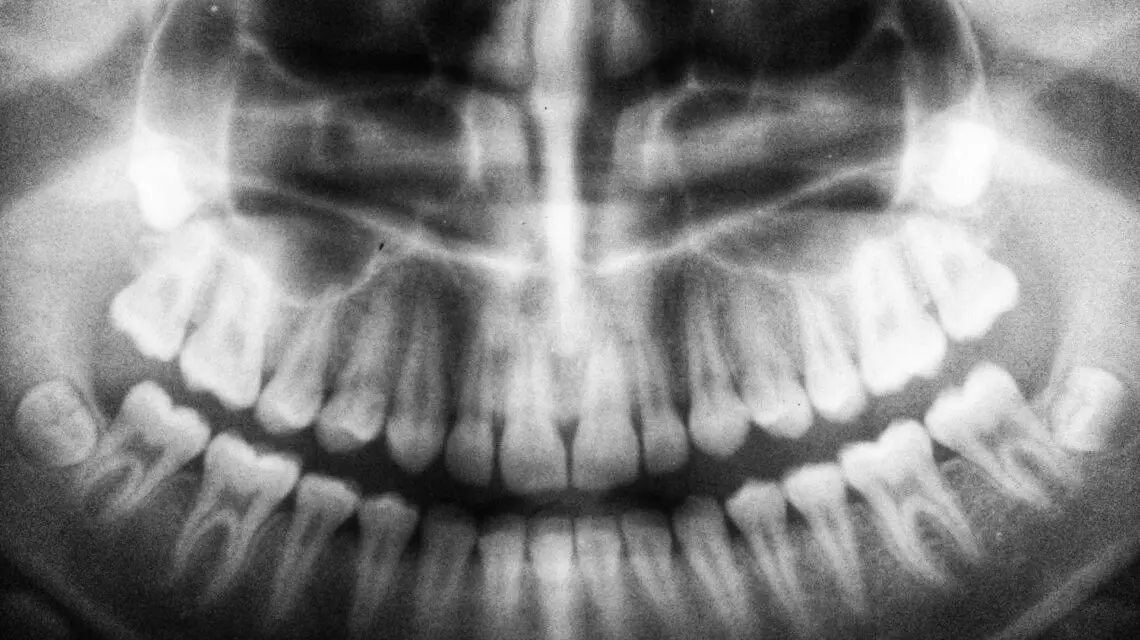

Your dentist may recommend removal based on your dental x-rays, the movement of your teeth, and your predisposition toward cavities or gum disease. The extraction can usually be performed by your dentist at their office. However, in some rare cases, you may have to see an oral surgeon.

If you are concerned about your wisdom teeth, having a conversation with a dentist should top your to-do list. Through x-rays and visual inspection, they will be able to accurately predict whether your wisdom teeth will cause problems in the future. They can advise you on whether your wisdom teeth should be removed or allowed to grow in.